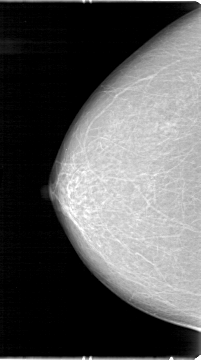

D_4042_1.RIGHT_CC

RIGHT_CC LINES 5386 PIXELS_PER_LINE 3001 BITS_PER_PIXEL 12 RESOLUTION 43.5 NON_OVERLAY